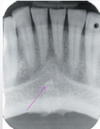

What radiolucent structure is pointed out in this picture?

Incisive Foramen